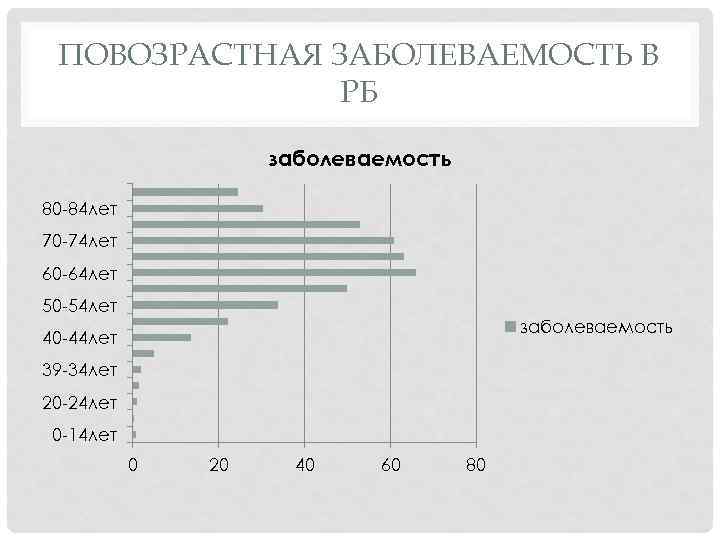

ПОВОЗРАСТНАЯ ЗАБОЛЕВАЕМОСТЬ В РБ заболеваемость 80 -84 лет 70 -74 лет 60 -64 лет 50 -54 лет заболеваемость 40 -44 лет 39 -34 лет 20 -24 лет 0 -14 лет 0 20 40 60 80